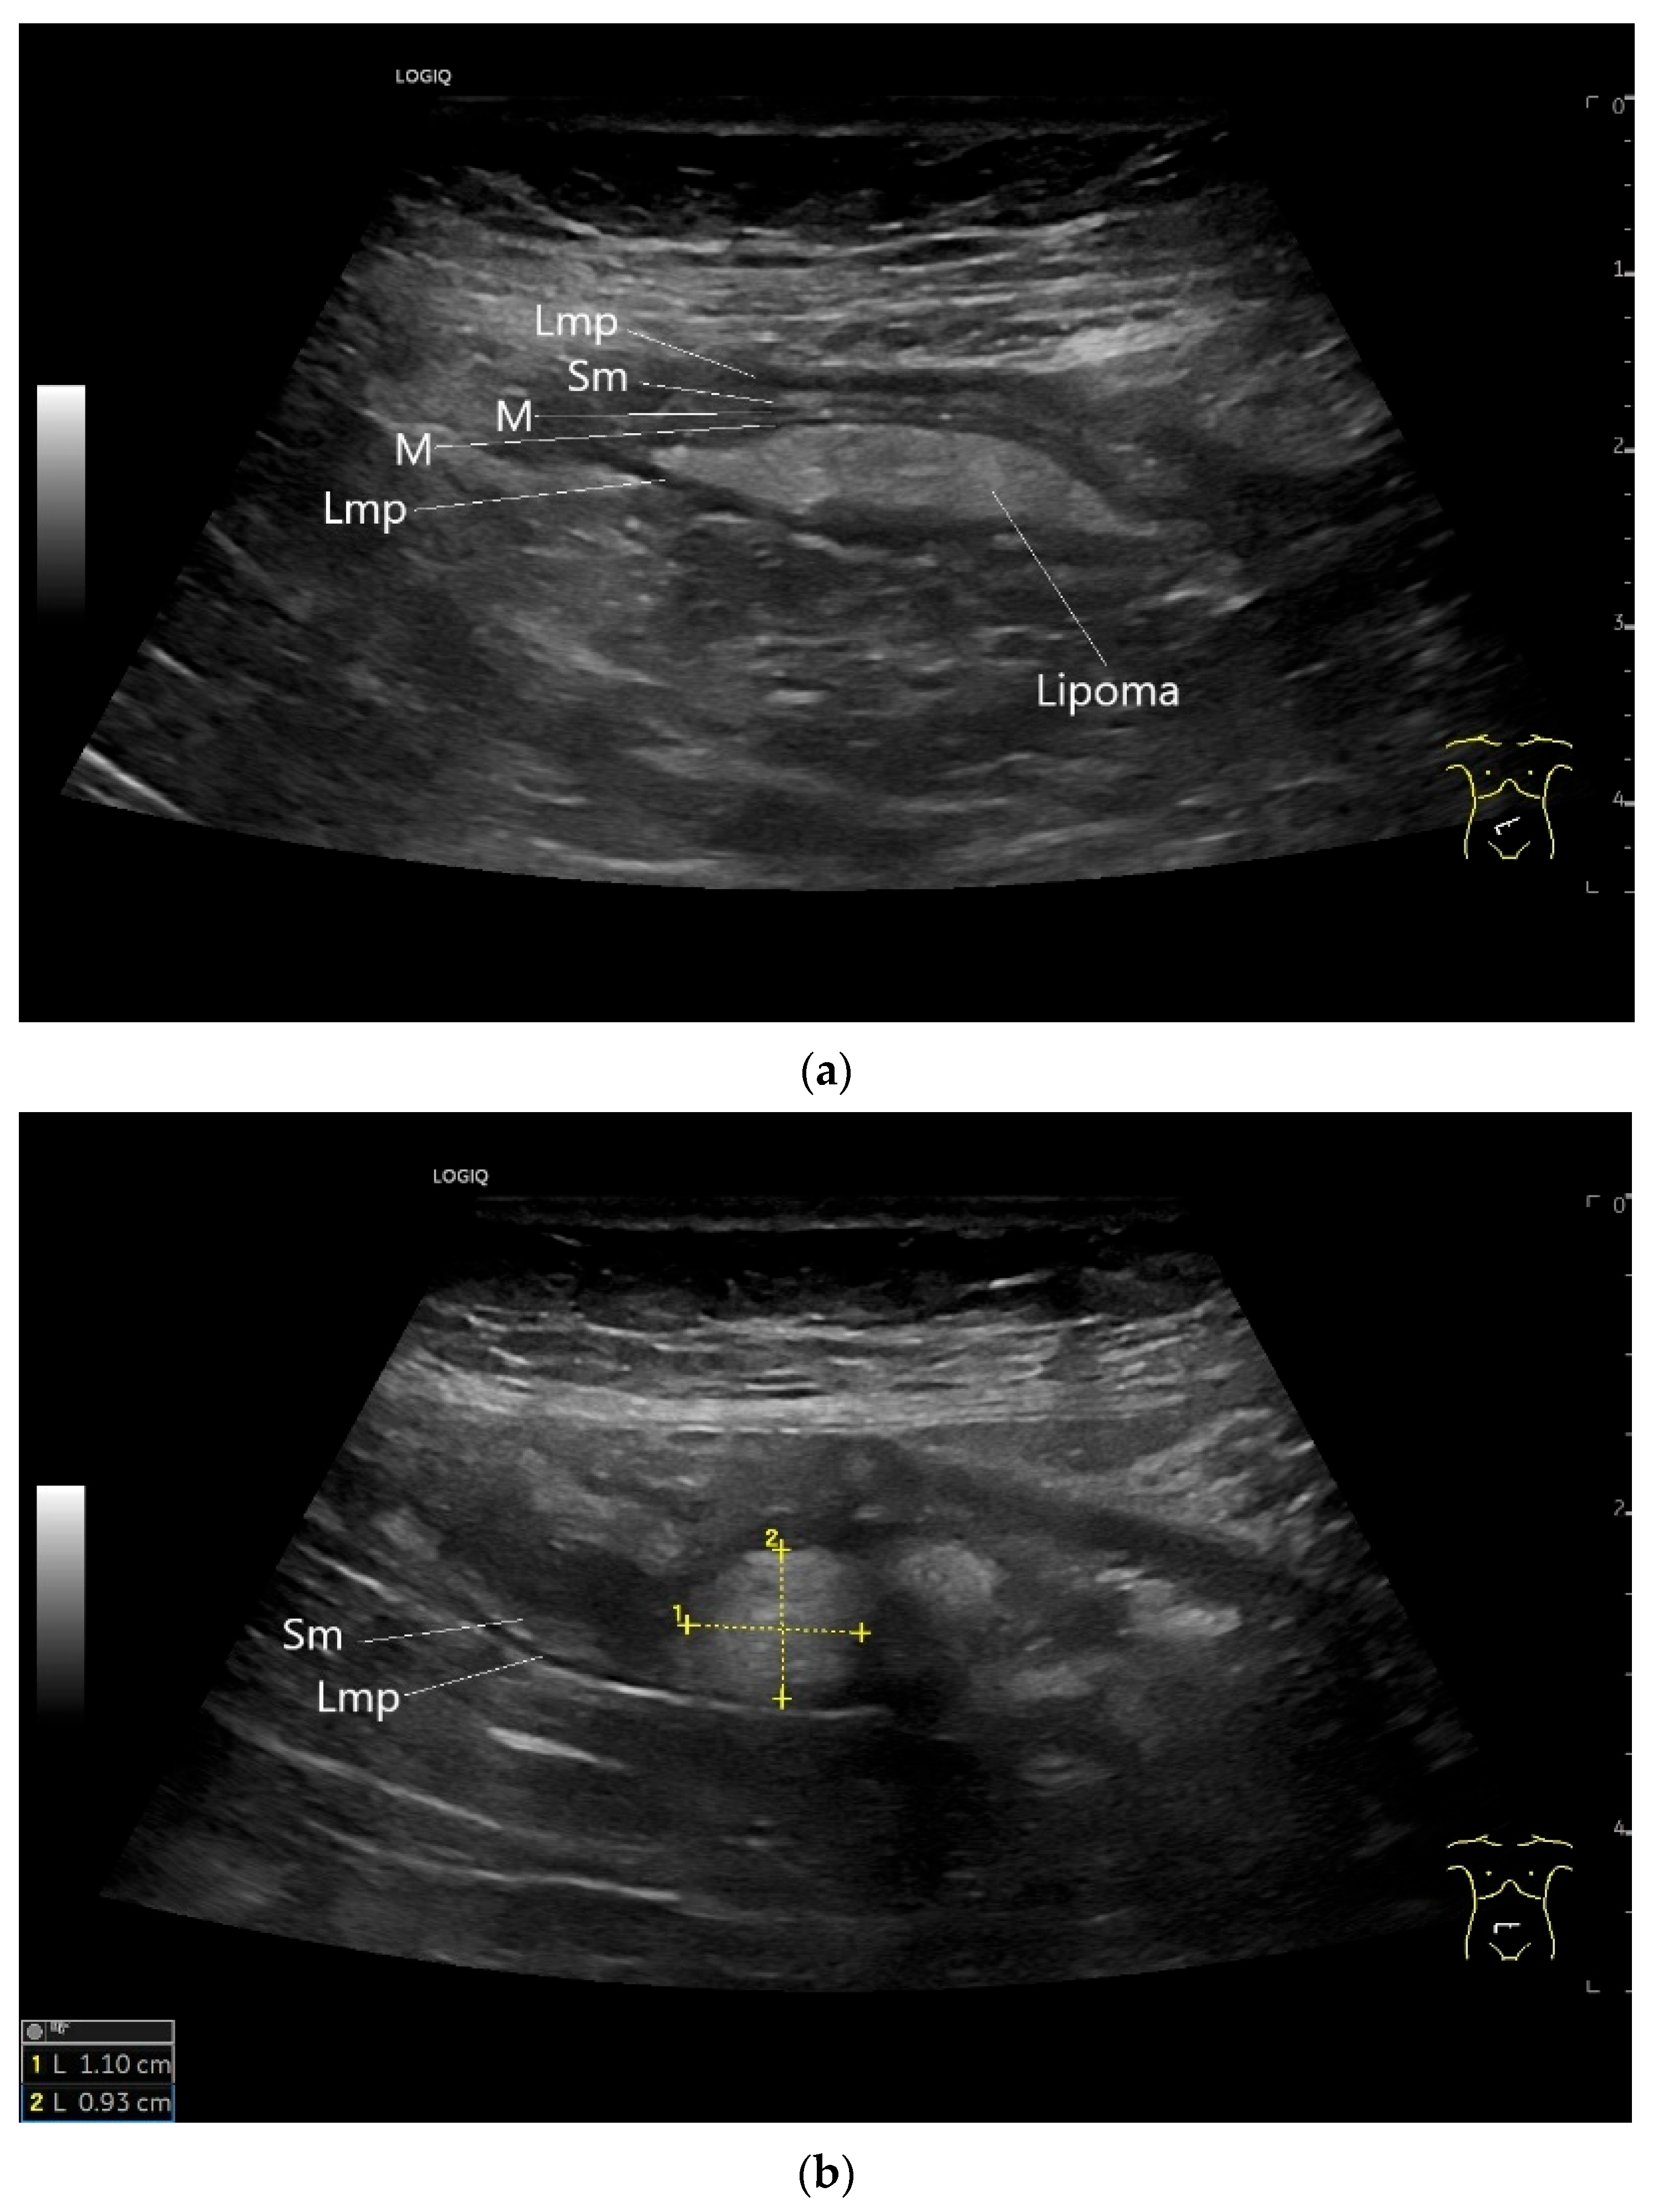

| Lipoma | Found in any part of the gastrointestinal tract. Rare in the small intestine and there predominantly located in the ileum. | Smoothly bordered oval/round lipomatous lesions, usually originating in the submucosa. Yellowish shimmering impressions on endoscopy, soft on contact. |

| Lymphangioma/lymphangiomatosis | Most commonly in the small intestine, followed by the colon and esophagus. | Either small (<2 cm) polypoid white or yellow mucosal lesions, usually discovered as incidentalomas, or larger masses with transmural spread or origin in the mesenterial adipose tissue. |

| GIST | Round hypoechoic masses, homogeneous or heterogeneous depending on size. They usually originate from the muscularis propria, which can be difficult to distinguish in US. Small vessels on CDI, hyperenhancement on CEUS. They move with the small intestine and can change position. |